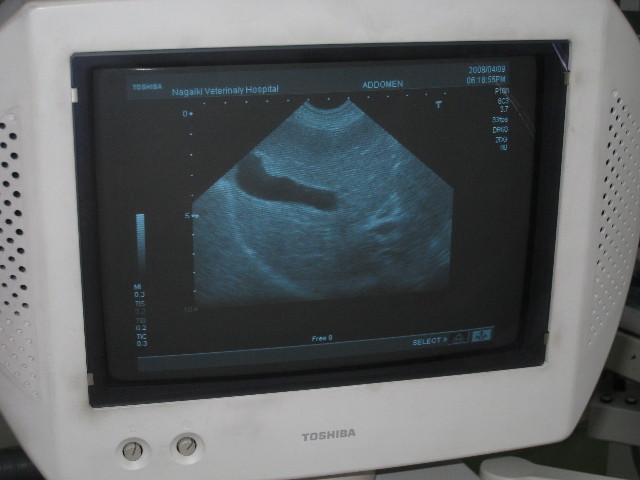

【エコー】

黒く写っているところが胆のう。

ちょっと場所を変えて、黒い胆のうの左の白っぽいのが胆泥。

胆泥は前より増えてしまっている。